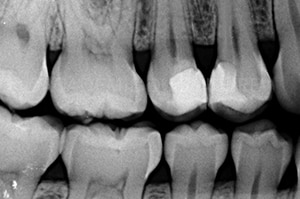

Fig 2.

L’analyse radiologique nous montre une proximité pulpaire des restaurations provisoires, surtout au niveau de la 15.